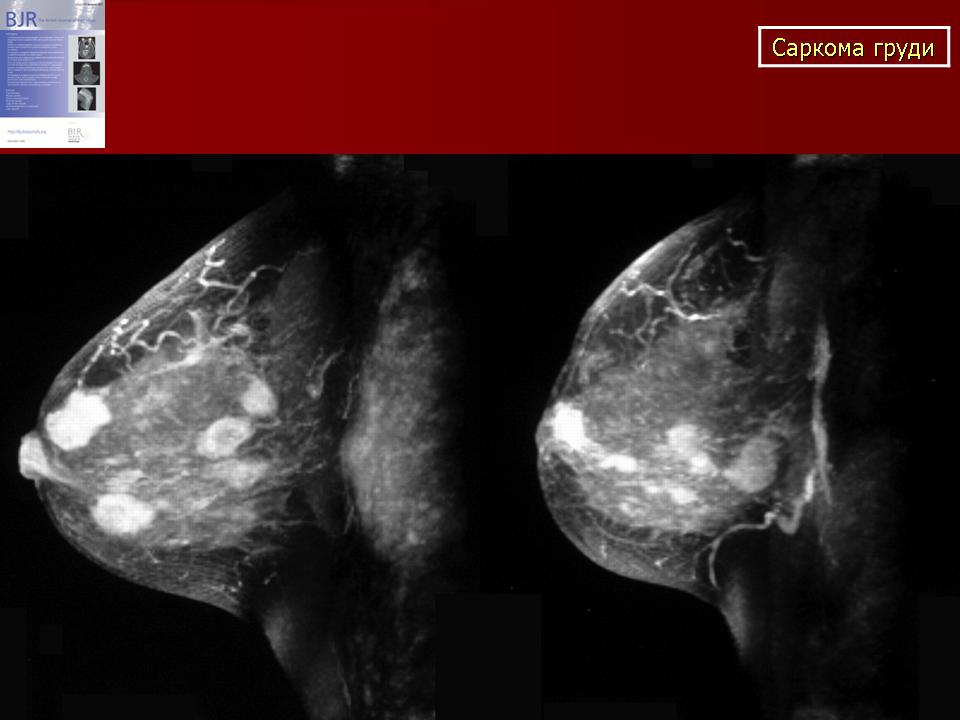

Магнитно-резонансная томография легких. Магниторезонансная томография легких. Магнитно ядерная томография. Ядерно-магнитно-резонансная томография. Саркома молочной железы на маммографии. Фибросаркома маммография. Саркома молочной железы рентген. Болезнь Педжета молочной железы маммография.

Саркома молочной железы на маммографии. Фибросаркома маммография. Саркома молочной железы рентген. Болезнь Педжета молочной железы маммография. Типы роста опухолей. Инфильтративный Тип роста. Инфильтрирующий рост опухоли.